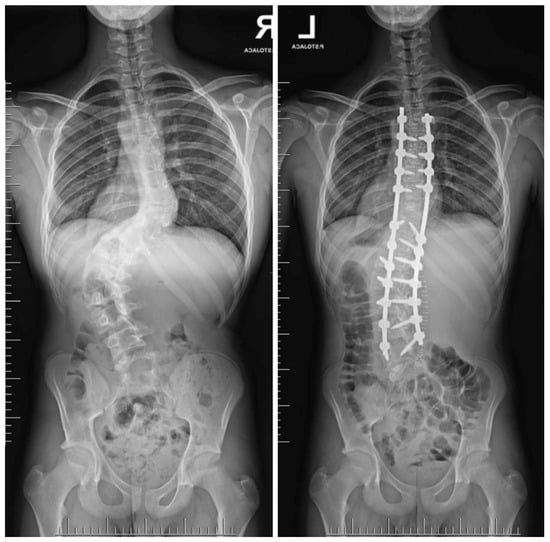

7.3.3. Hemivertebrectomy

7.3.4. Growing Rod Systems